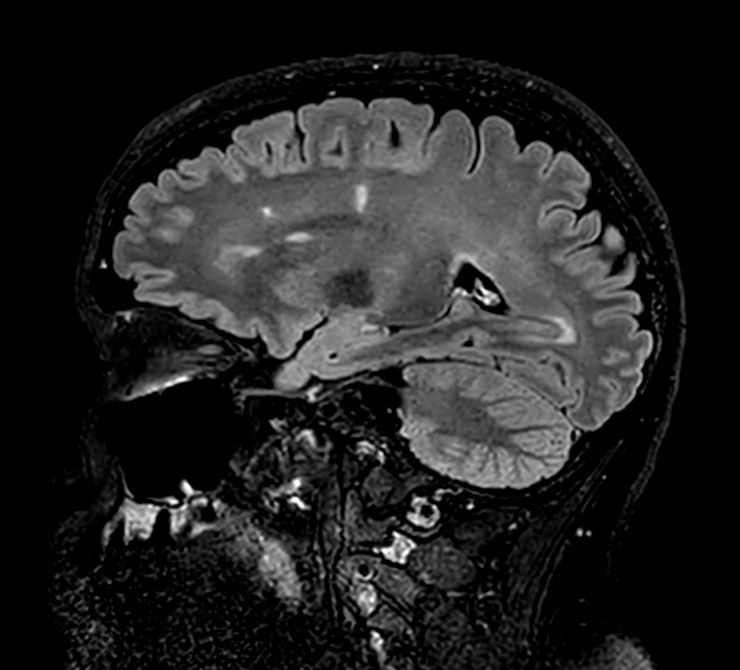

Axial 3D VIEW - T2w FLAIR

-